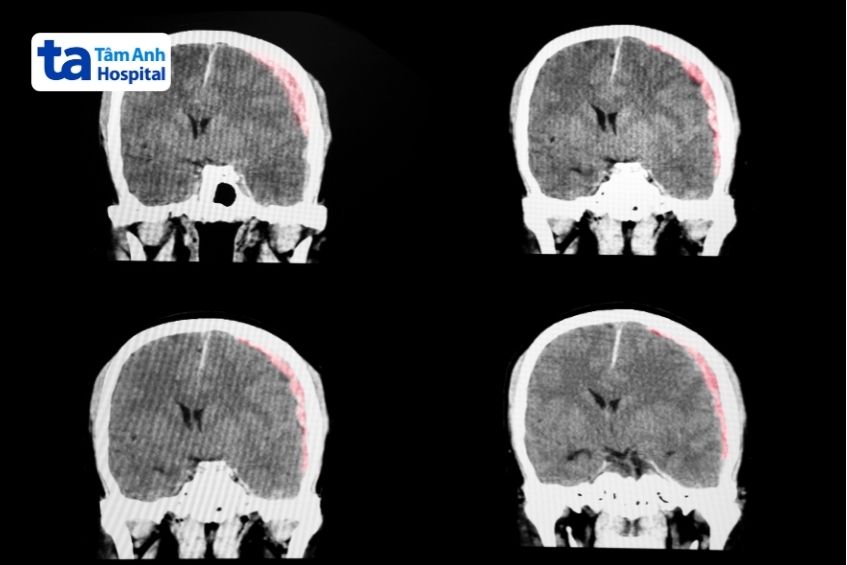

Chấn thương sọ não bao lâu thì hồi phục còn tùy thuộc vào mức độ tổn thương não…